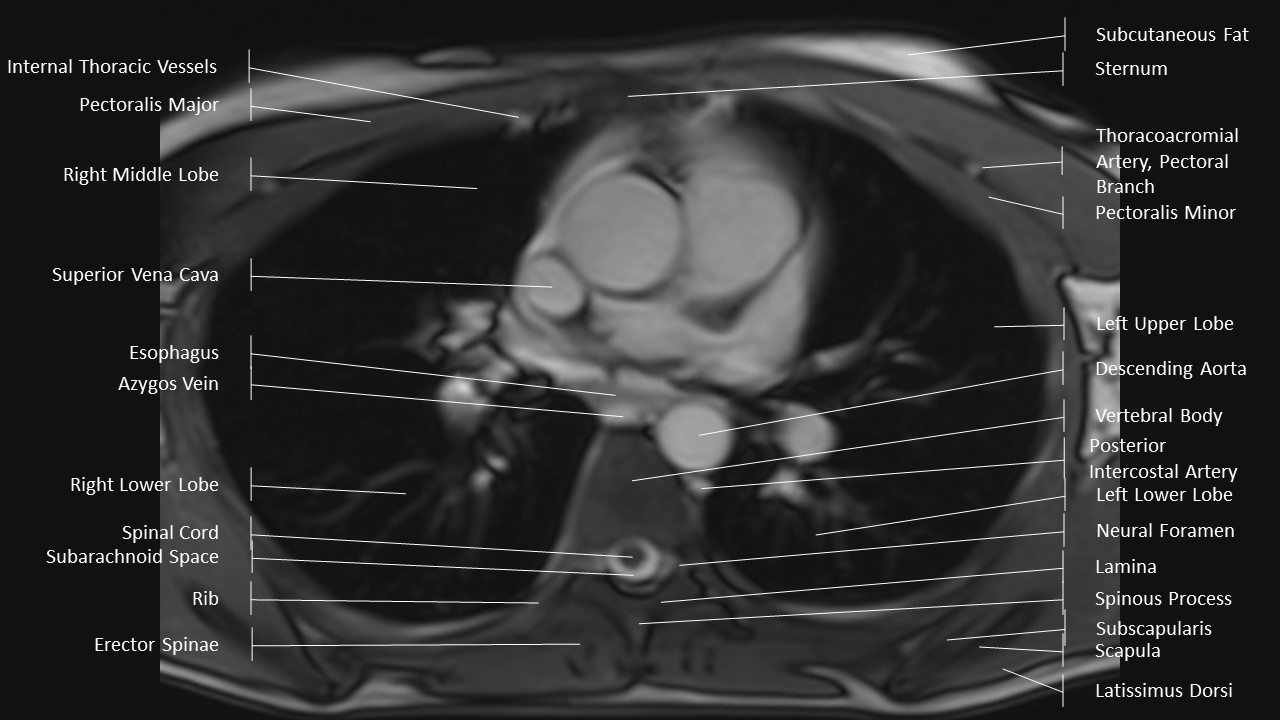

Axial Series